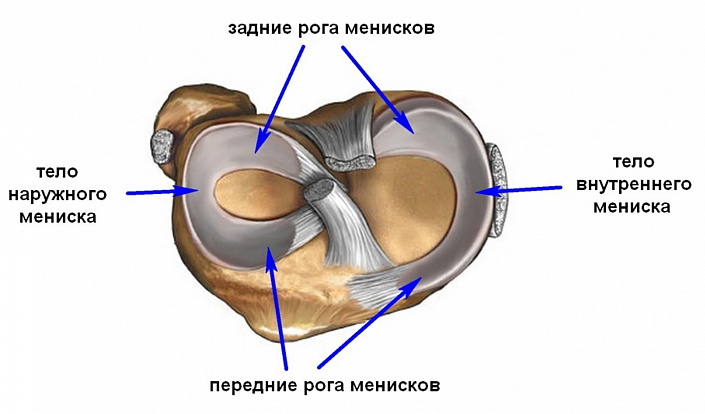

Поскольку примыкающие друг к другу трубчатые кости, формирующие колено, несоразмерны ни по площади, ни по форме поверхности, между ними необходимо что-то, что будет компенсировать эту несовместимость, выполняя функцию своеобразного амортизатора. Именно эту роль играют мениски — небольшие гибкие образования, которые поддерживают устойчивость сустава, равномерно распределяя нагрузку на прилежащие поверхности костей. Свободные края позволяют им беспрепятственно передвигаться в полости сустава.

Несмотря на то, что анатомическое строение менисков напоминает хрящевую ткань, да и во многих справочниках их относят именно к хрящам, сами образования немного отличаются от обычных хрящиков: они более гибкие, поскольку включают высокий процент эластиновых волокон. Именно благодаря этому им удаётся обеспечивать полноценное взаимодействие костей под высокой нагрузкой, препятствуя их истиранию и деформации. Поэтому при малейшей травме менисков страдает весь сустав, включая костные структуры.